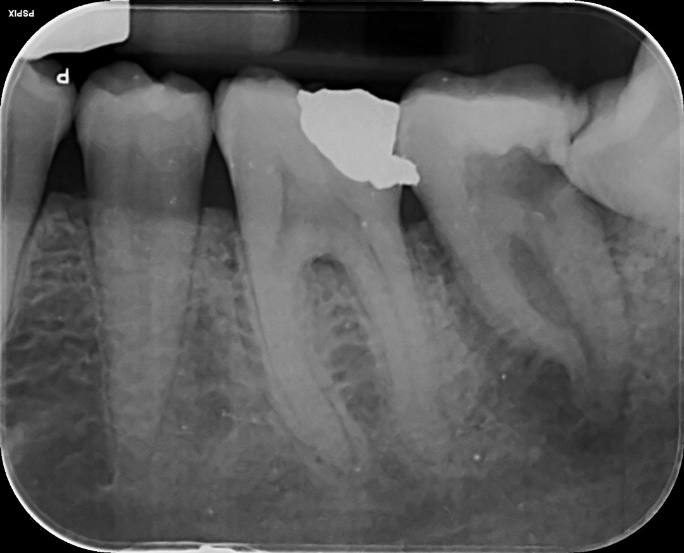

Lower Molar x2 curved roots Primary Root canal treatment and dental crown/rebuild